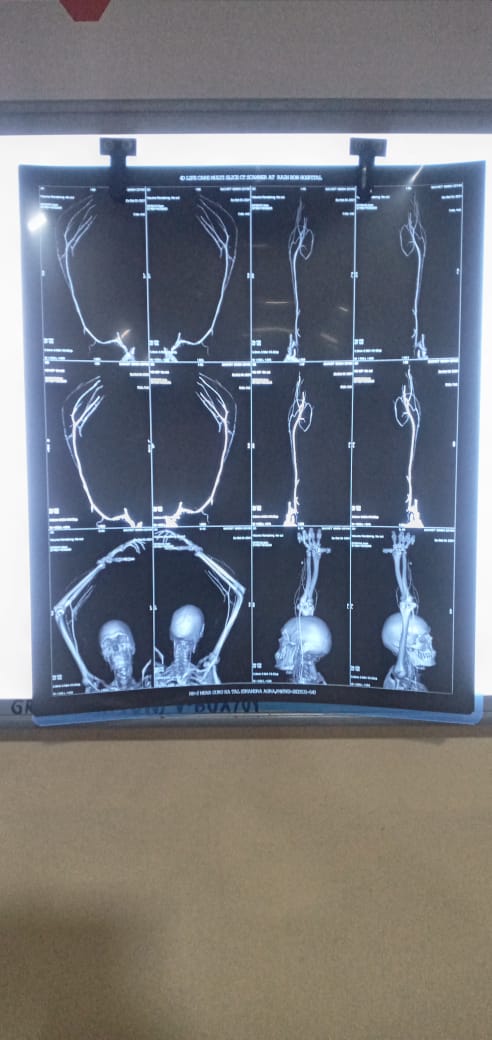

Photo Gallery Dr. Monika Gupta - Photo Gallery 7 5 2 8 6 Dr. Atul Kumar Gupta - Photo Gallery « ‹ of 3 › » Video Gallery